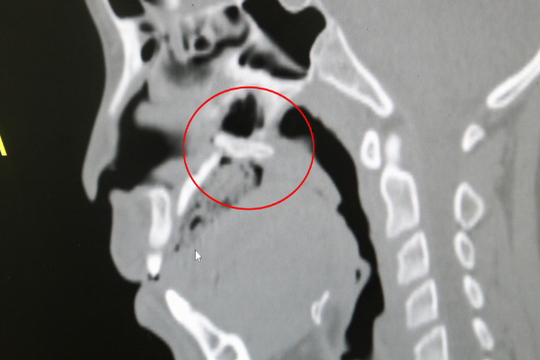

Bé trai 10 tuổi thủng vòm họng do ngã xe đạp

Bé trai ở Quảng Ninh bị thủng vòm họng, chấn thương nặng, chảy máu nhiều do ngã xe đạp khiến tay lái đâm vào miệng.